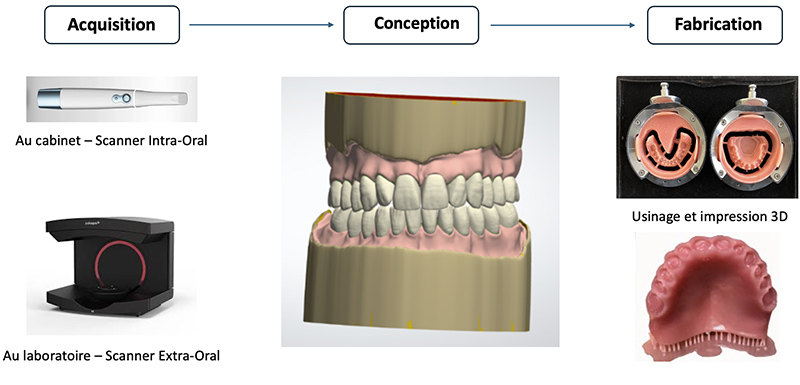

Fig. 01 : le flux numérique en prothèse amovible complète.

L’acquisition des données cliniques du patient constitue le premier maillon de la chaîne numérique en prothèse amovible complète. Elle permet de transformer les informations cliniques nécessaires à la réalisation prothétique en données exploitables dans un flux de conception et de fabrication assistées par ordinateur. Cette étape peut être réalisée soit au laboratoire de prothèse, soit directement au cabinet dentaire, selon les protocoles retenus.

Au laboratoire, l’acquisition des données est le plus souvent réalisée à l’aide d’un scanner extra-oral, permettant la numérisation d’empreintes physico-chimiques, de modèles en plâtre, de porte-empreintes individuels, de maquettes d’occlusion ou encore de prothèses amovibles complètes existantes. Cette modalité s’inscrit généralement dans des flux de travail hybrides, associant des étapes cliniques réalisées selon des protocoles conventionnels à une exploitation numérique des données au laboratoire de prothèse, notamment lors des phases de conception et de fabrication assistées par ordinateur.

Au cabinet dentaire, l’acquisition peut être réalisée à l’aide d’une caméra, par le biais d’une empreinte optique. Utilisée en mode extra-oral, elle permet la numérisation d’empreintes physico-chimiques ou de prothèses existantes.

Les fichiers issus de cette phase d’acquisition sont alors transmis à un logiciel de Conception Assistée par ordinateur (CAO), permettant la modélisation virtuelle de porte-empreintes individuels, de maquettes d’occlusion, de maquettes d’essayage et des prothèses amovibles complètes.

Les données numériques générées au cours de cette phase de conception sont ensuite exportées vers un logiciel de Fabrication Assistée par Ordinateur (FAO), qui pilote une machine-outil à commande numérique chargée de la réalisation des prothèses amovibles complètes, soit par soustraction de matière à l’aide d’une unité d’usinage, soit par addition de matière selon les principes de l’impression 3D.